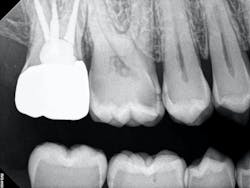

The iTero scanner was able to clearly define the delineation between the soft and hard tissue as can be seen in this image of the digital die trim (figure 3). Radiographs were captured on delivery revealing a clinically acceptable outcome for the patient (figure 4). Direct restorations were completed on teeth Nos. 3 and 4 during this visit.